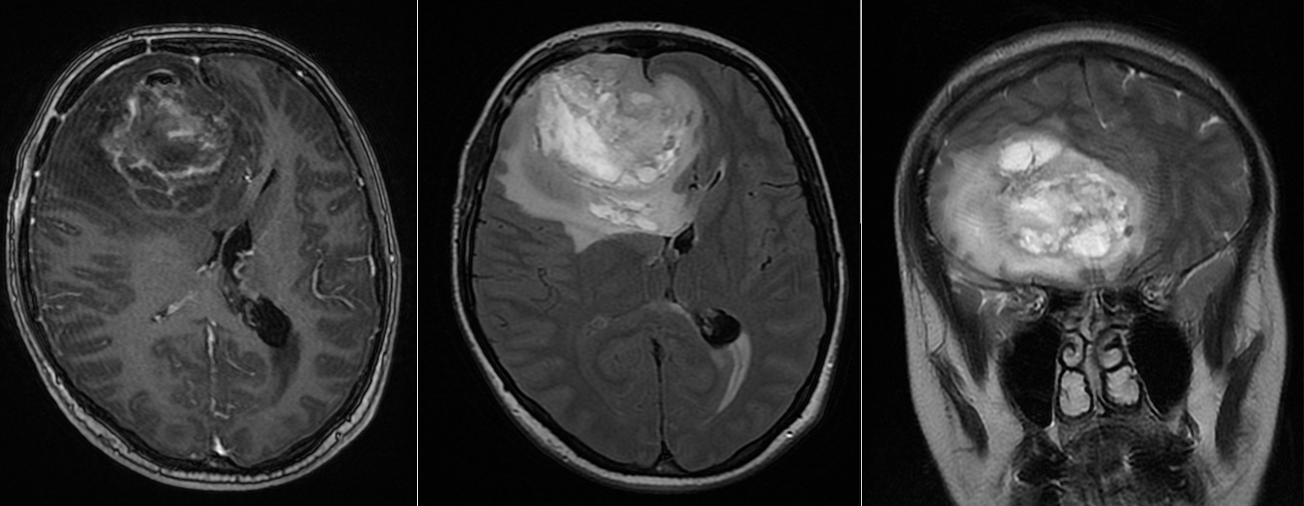

Tipul exact al unei tumori cerebrale nu poate fi stabilit doar pe baza simptomelor. Investigația principală este RMN-ul cerebral, care oferă informații despre localizarea, dimensiunea și caracteristicile formațiunii. Totuși, diagnosticul definitiv se stabilește prin analiza microscopică a țesutului tumoral, realizată de medicul anatomopatolog după intervenția chirurgicală sau după o biopsie. Această analiză permite identificarea exactă a tipului de tumoră și a gradului ei de agresivitate, conform clasificării actuale OMS. Pe baza acestor informații se stabilește strategia optimă de tratament.